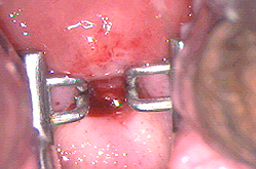

Se han utilizado el electrocauterio y el asa diatérmica para la electrocauterización de las lesiones con una tasa real de éxito muy regular pues existe curación en el 93% de los pacientes, pero el 24% vuelven a presentar las lesiones en menos de 2 años, por lo que la tasa real de éxito es del 69%, y además tienen el inconveniente de ser muy dolorosos ya que no existe un control preciso de la profundidad con la que se destruye la piel por lo que penetran más de 1 mm, y afecta las terminaciones nerviosas, debido a esto los pacientes presentan dolor en los genitales externos, (las mujeres en vulva y los varones en pene) cuando practican deportes que ocasionan fricción en la zona o cuando tienen relaciones sexuales y esto puede durar hasta varios meses. Debido a las secuelas actualmente no se recomiendan dichos procedimientos para tratar los siguientes órganos: vagina, vulva, periné, región peri anal, ano y pene, con lesiones extensas.